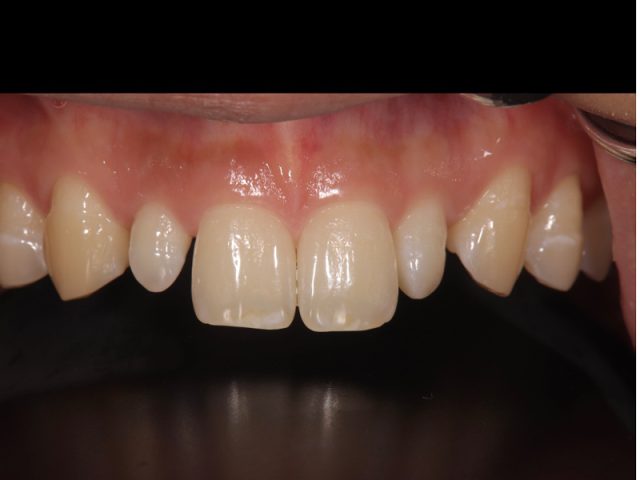

前歯の被せ物のやり替え治療(オールセラミック)

Before

After

| 診断名 | 前歯の審美補綴治療 |

|---|---|

| 年齢・性別 | 40代・男性 |

| 治療期間・回数 | 半年/10回 |

| 治療方法 | 審美補綴治療(オールセラミック) |

| 費用 | セラミックス補綴(1歯):165,000円(税込み) 歯周外科(1ブロック):110,000円(税込み) |

| デメリット・注意点 | 保険が適用できないため自費診療になる。 セラミックスインレー・クラウンに強い力がかかると割れてしまう恐れがあるため、歯ぎしりや食いしばりが癖になっている患者様にはおすすめできない場合がある |